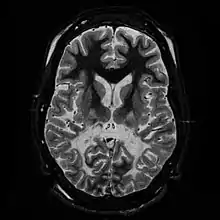

| T2 weighted axial scan of a human brain at the level of the caudate heads demonstrates marked loss of posterior white matter, with reduced volume and increased signal intensity. The anterior white matter is spared. Features are consistent with X-linked adrenoleukodystrophy. | |

The degeneration of white matter, which reflects the degeneration of myelin, can be seen in a basic MRI and used to diagnose leukodystrophies of all types. T-1 and T-2 weighted fluid-attenuated inversion recovery (FLAIR) images are the most often used approach.[24] Electrophysiological and other kinds of laboratory testing can also be done. In particular, nerve conduction velocity is looked at to distinguish between leukodystrophy and other demyelinating diseases, as well as to distinguish between individual leukodystrophies. For example, individuals with X-ALD have normal conduction velocities, while those with Krabbe disease or metachromatic leukodystrophy have abnormalities in their conduction velocities.[24] Multigene sequencing panels for undifferentiated leukodystrophy are offered for rapid molecular diagnosis after genetic counselling.